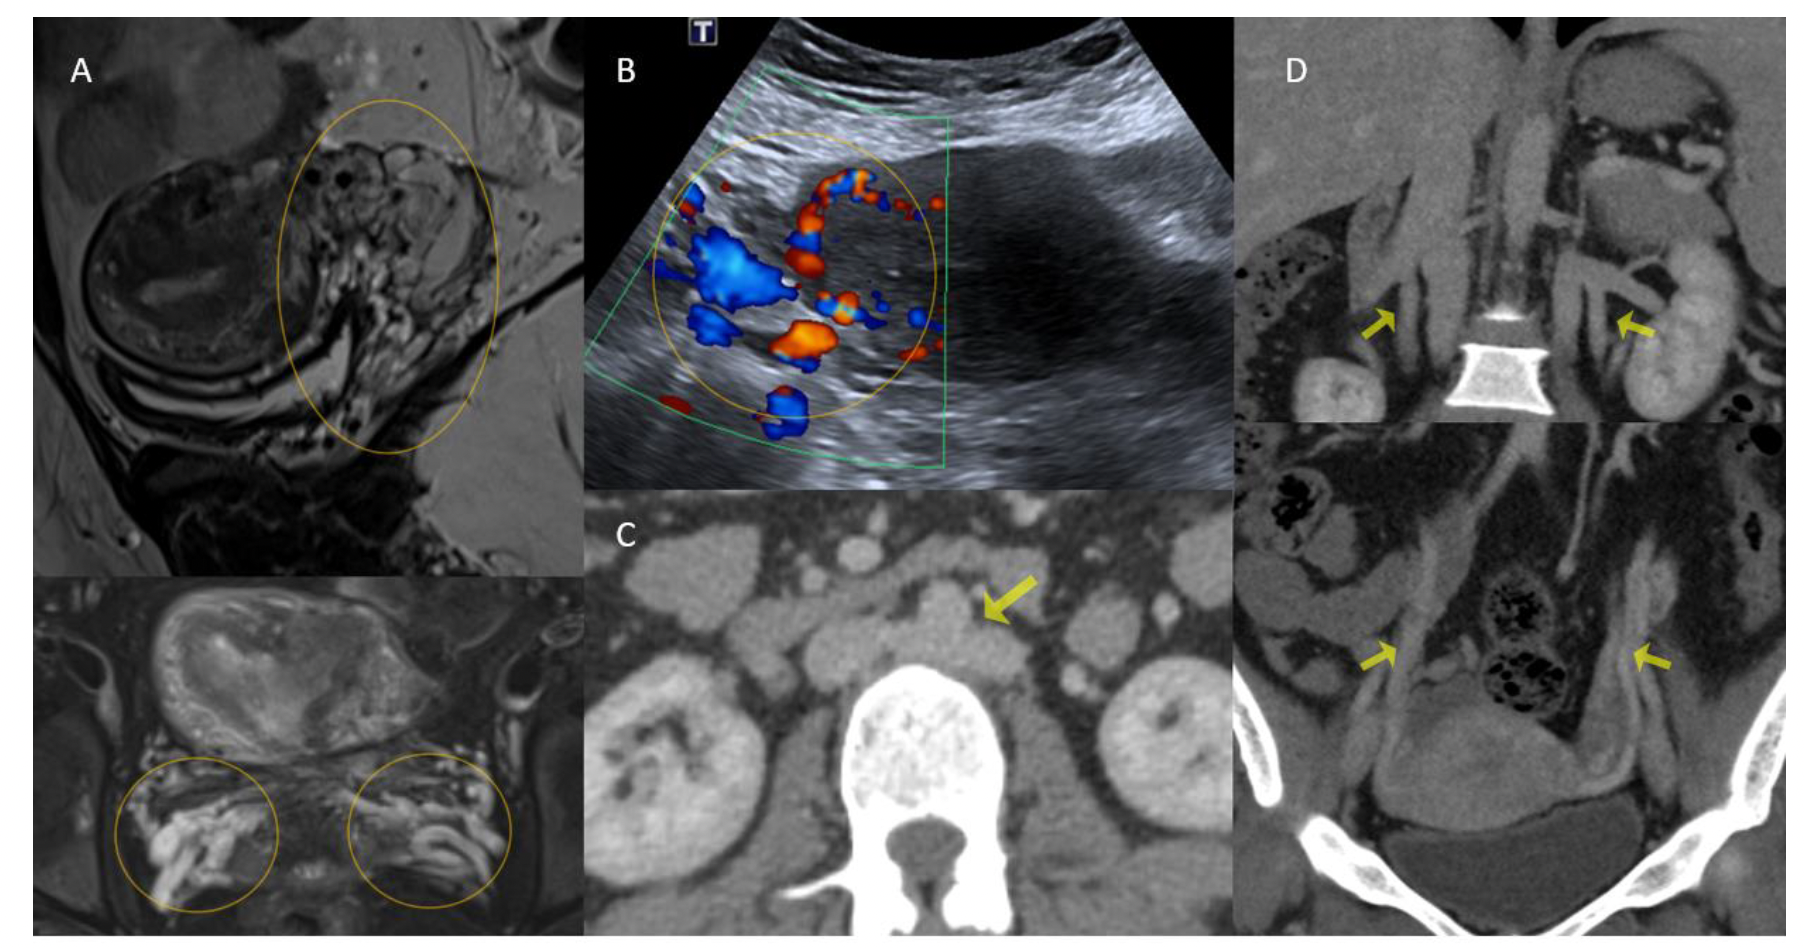

The patient’s previous contrast-enhanced computed tomography (CECT) scan was reviewed (Figure 1), showing duplication of the inferior vena cava (IVC). The left common iliac vein was continuing as the left IVC, which was communicating with the right IVC through retroperitoneal collaterals in the lumbar region. The left internal iliac vein (IIV) was joining the right IIV. The right IIV (a common trunk for both IIVs) was extrinsically compressed by the right common iliac artery (Figure 2). Both gonadal veins were dilated. Magnetic resonance imaging of the pelvis showed persistent flow voids in the parametrium and adnexa, consistent with pelvic venous congestion (Figure 1).

Endovascular treatment was planned. Under aseptic precautions, the right internal jugular vein was accessed and a 5F sheath was placed. Using a 0.035" guidewire and 5F multipurpose catheter, the left IIV was cannulated. The venogram (Figure 3) showed significant extrinsic compression stenosis in the junction of the common venous trunk, correlating with the CECT (Figure 2). Multiple venous collaterals were seen in the pelvis with stagnation of the contrast.

On-table intravascular ultrasound (IVUS) confirmed the findings (Figure 2). The diameter of the venous trunk was 13.4 mm caudal to the narrowing. There was a pressure gradient of 5 mm Hg across the narrowing. A 16 mm x 6 cm Wallstent endoprosthesis self-expanding stent (Boston Scientific) was deployed across the narrowed portion of the common venous trunk (Figure 4). The stent was opened with a 14 mm x 4 cm balloon. Check venogram showed a brisk antegrade flow. The pressure gradient had reduced to 2 mm Hg. The patient had an uneventful recovery and was asymptomatic on follow-up at 6 months.